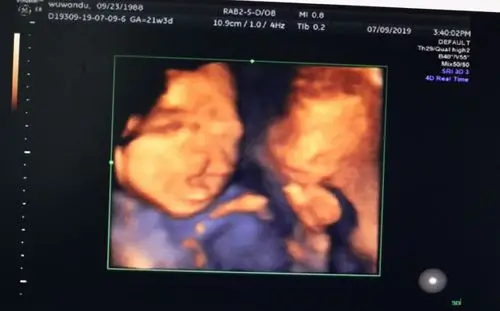

全前脑畸形(holoprosencephaly)也称前脑无裂畸形,是前脑发育障碍引起

全前脑并单鼻孔)▼(胎儿唇裂)▼(部分案例)以下是通过我院美国ge-e8